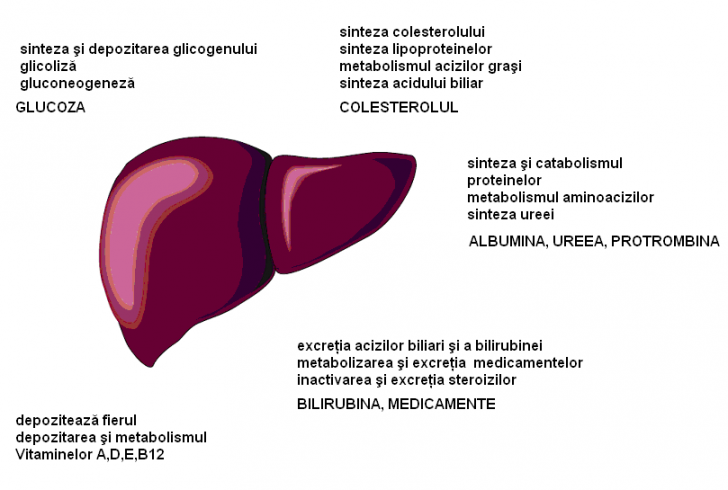

INSUFISIENTA HEPATICA

INSUFISIENTA HEPATICA Insuficienta hetatica (IF) reprezinta reducerea semnificativa a functiilor hepatice, cu potential letal. Simptomatologia apare atunci cand capacitatea functionala hepatic�Citeste tot ... 2730 cuvinte

Dimensiune medie

+ cu poze |